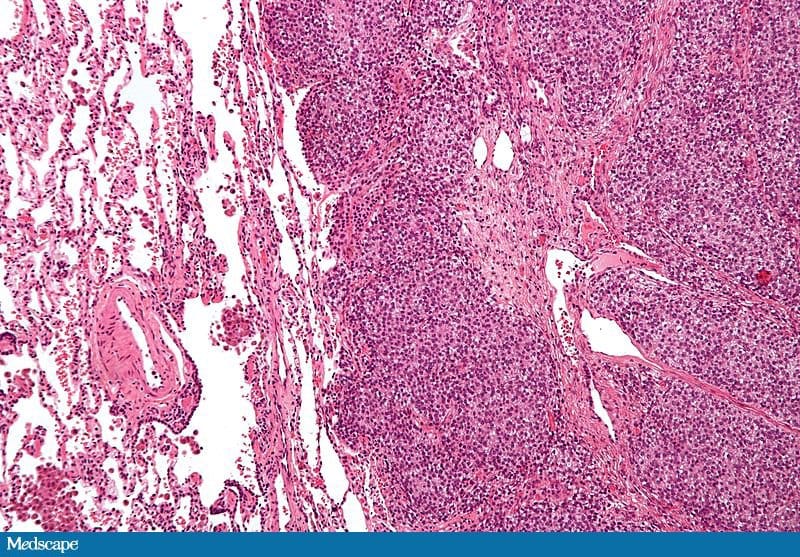

O sarcoma de Ewing é um tumor maligno dos ossos e partes moles cuja origem é presumivelmente mesenquimal; é tipicamente diagnosticado na segunda década de vida. [4,5] Histologicamente, o sarcoma de Ewing é formado por pequenas células hipercromáticas redondas ou ovaladas com pouquíssimo citoplasma (Figura 2). Em 75% dos casos os resultados de coloração por PAS são positivos. A superexpressão da proteína de superfície da membrana CD99 é uma característica universal do sarcoma de Ewing; embora semelhante à coloração por PAS, não é inteiramente específica (Figura 3). [6,7]

Figura 2.